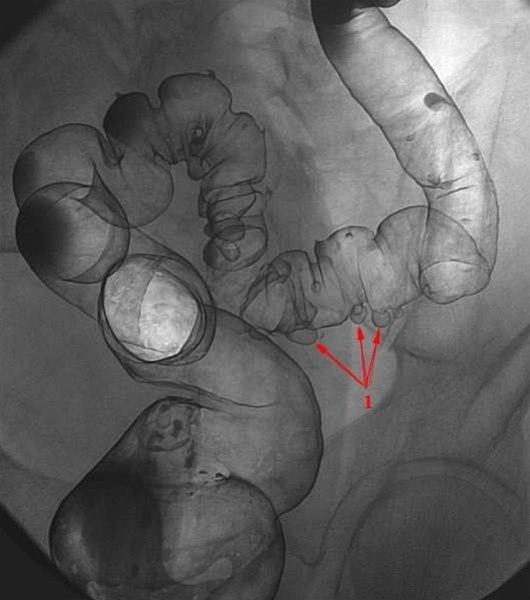

Dobbelkontrastbilde av rektum og sigmoideum med multiple divertikler i varierende størrelser (1).